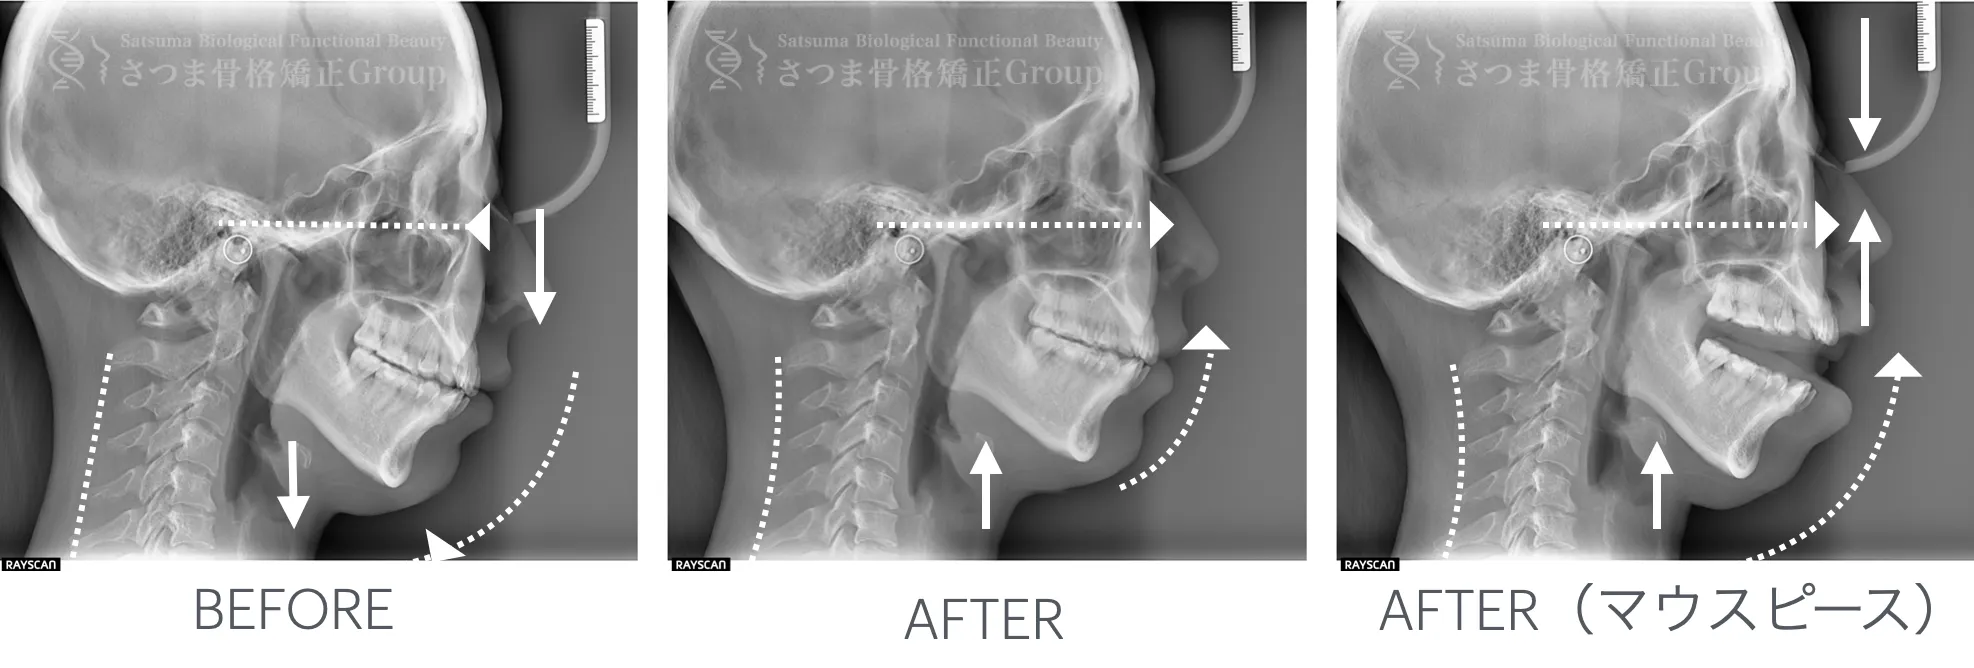

最新のCTスキャンによる顎・顔面・頚椎の立体画像検査を導入。

治療前後の変化を視覚的に確認できるため、

改善のプロセスを“見てわかる”形で効果を実感いただけます。